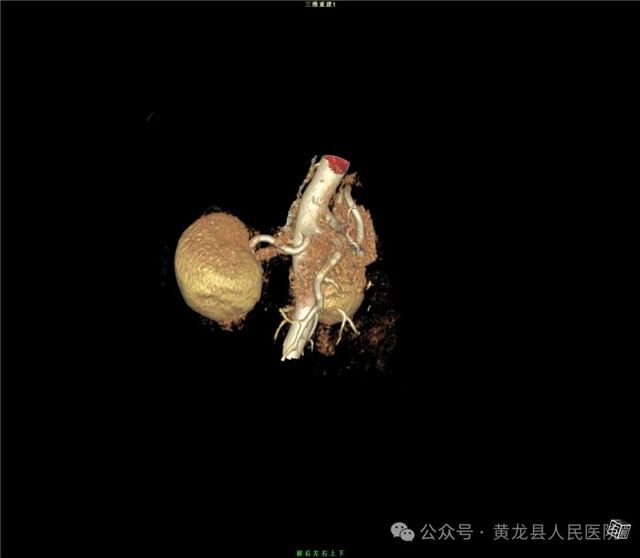

双肾VR

患者男性,70岁,因“发现右肾肿物1年余”收住于我院外科,经查体及相关检查后诊断为:右肾肿瘤。为尽早解除患者疾病困扰,方继荣主任迅速组织泌尿外科、手麻科、普外科等多学科进行会诊,对患者的病情进行了全面而深入的评估。最终确定详细周密手术方案,将患者病情及治疗方法告知患者及家属征得同意后,由我院泌尿外科刘涛主治医师实施手术。